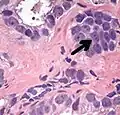

-

Intraductal carcinoma of the prostate with an infiltrative growth pattern may be morphologically difficult to distinguish from invasive cancer. One focus shows comedonecrosis (arrow), morphologically suggesting Gleason pattern 5 invasive carcinoma (a haematoxylin and eosin, b CK5/6)[20] -